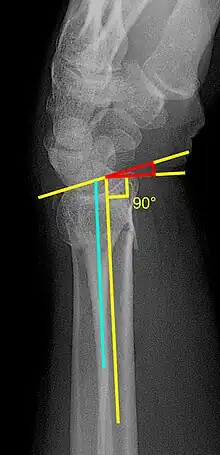

Fracture with a dorsal tilt: Dorsal is left, and volar is right in the image.

X-ray of the affected wrist is required if a fracture is suspected. Posteroanterior, lateral, and oblique views can be used together to describe the fracture.[5] X-ray of the uninjured wrist should also be taken to determine if any normal anatomic variations exist before surgery.[5]

• Volar or dorsal tilt - A line is drawn joining the most distal ends of the volar and dorsal side of the radius. Another line perpendicular to the longitudinal axis of the radius is drawn. The angle between the two lines is the angle of volar or dorsal tilt of the wrist. Measurement of volar or dorsal tilt should be made in true lateral view of the wrist because pronation of the forearm reduces the volar tilt and supination increases it. When dorsal tilt is more than 11 degrees, it is associated with loss of grip strength and loss of wrist flexion.[5]